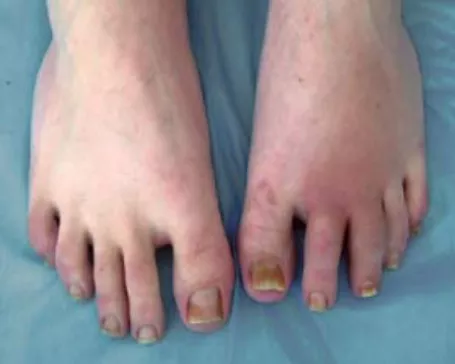

Рисунок 3. Асимметричное поражение суставов стоп при псориатическом артрите. Артрит 2-го, 3-го ПлФС левой стопы, 3-го левого ПМФС левой стопы, дактилит V пальца правой стопы

Рисунок 6. Артрит ДМФС стоп, редискообразная деформация II пальца правой стопы у больного ранним псориатическим артритом в сочетании с псориазом ногтей (онихолизис, онихомадез)

Рисунок 7. Мутилирующая форма псориатического артрита. Разнонаправленные подвывихи суставов кистей, деформация по типу "шеи лебедя" (II, III, IV пальцы правой кисти), укорочение III, V пальцев левой кисти в результате резорбции кости